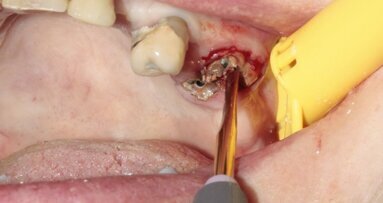

This was a challenging case with the combined issues of a failed root canal therapy and an iatrogenic perforation of the floor of the pulp chamber. Though ...